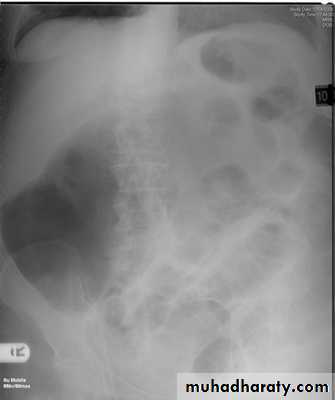

Intestinal gas pattern

Relatively large amounts of gas are usually present in the stomach and colon in a normal patient.The stomach can be readily identified by it's location, gastric rugae in the supine view , and by the air fluid level beneath the left hemidiaphragm in the erect view

Dilatation of the bowel

Dilatation of the bowel is the cardinal plain film sign of intestinal obstruction

If the bowel is dilated it is important to try and decide which portion is involved

The valvulae conniventes (seen in proximal and mid small bowel) are always closer together than the colonic haustra and cross the width of the bowel , often giving "stack of coins" appearance

The colonic haustra ,which usually form incomplete bands across the colonic gas shadows, are always present in the ascending and transverse colon, but may be absent distal to the splenic flexure